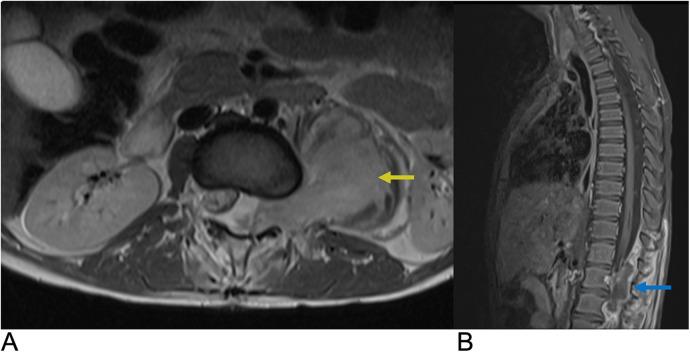

Spinal lesions encompass a diverse range of pathologies, including primary and secondary tumors, infectious processes, vascular malformations, traumatic injuries, and degenerative conditions, each with distinct imaging characteristics crucial for accurate diagnosis and management. Imaging plays vital roles in assessing lesion morphology, anatomical localization, and neurological impact, guiding clinical decision-making and therapeutic planning. This review systematically explores spinal lesions based on their anatomical compartments, highlighting key radiological features and providing a comprehensive reference for radiologists.

脊柱病变包括多种病理情况,包括原发性和继发性肿瘤、感染性病变、血管畸形、创伤性损伤以及退行性疾病,每种病变都具有独特的影像学特征,这些特征对于准确诊断和治疗至关重要。影像学在评估病变形态、解剖定位和神经影响方面发挥着至关重要的作用,指导临床决策和治疗规划。本综述基于解剖分区系统地探讨脊柱病变,突出关键的放射学特征,并为放射科医生提供全面的参考。